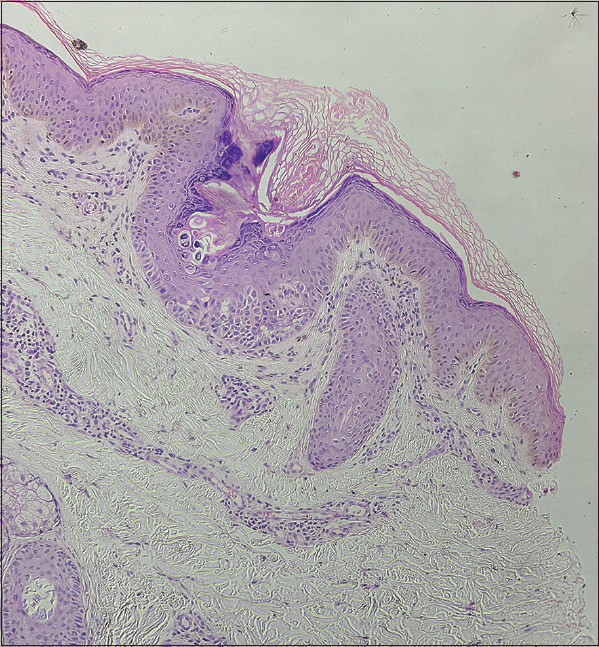

Familial Follicular Keratotic Papules in a Young Male.

年轻男性的家族性滤泡性角化丘疹。